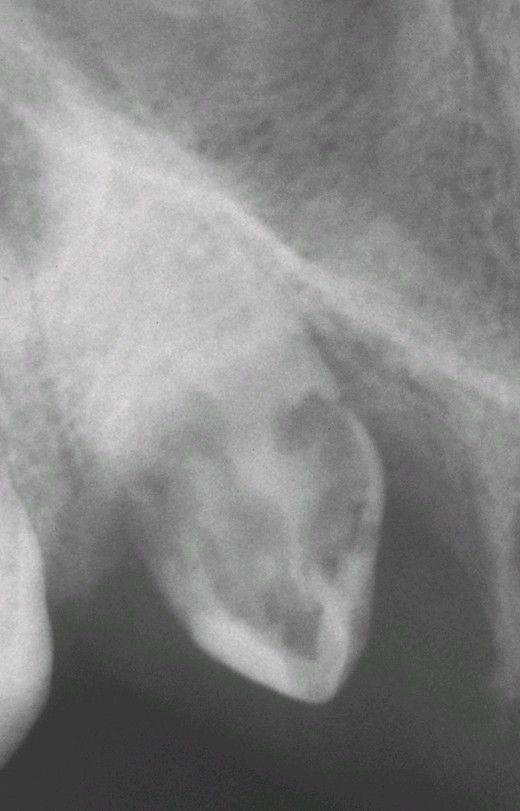

External resorption

Extensive external resorption of the crown of the impacted right maxillary cuspid. Histopathologic examination revealed resorption without bacterial contamination or caries.